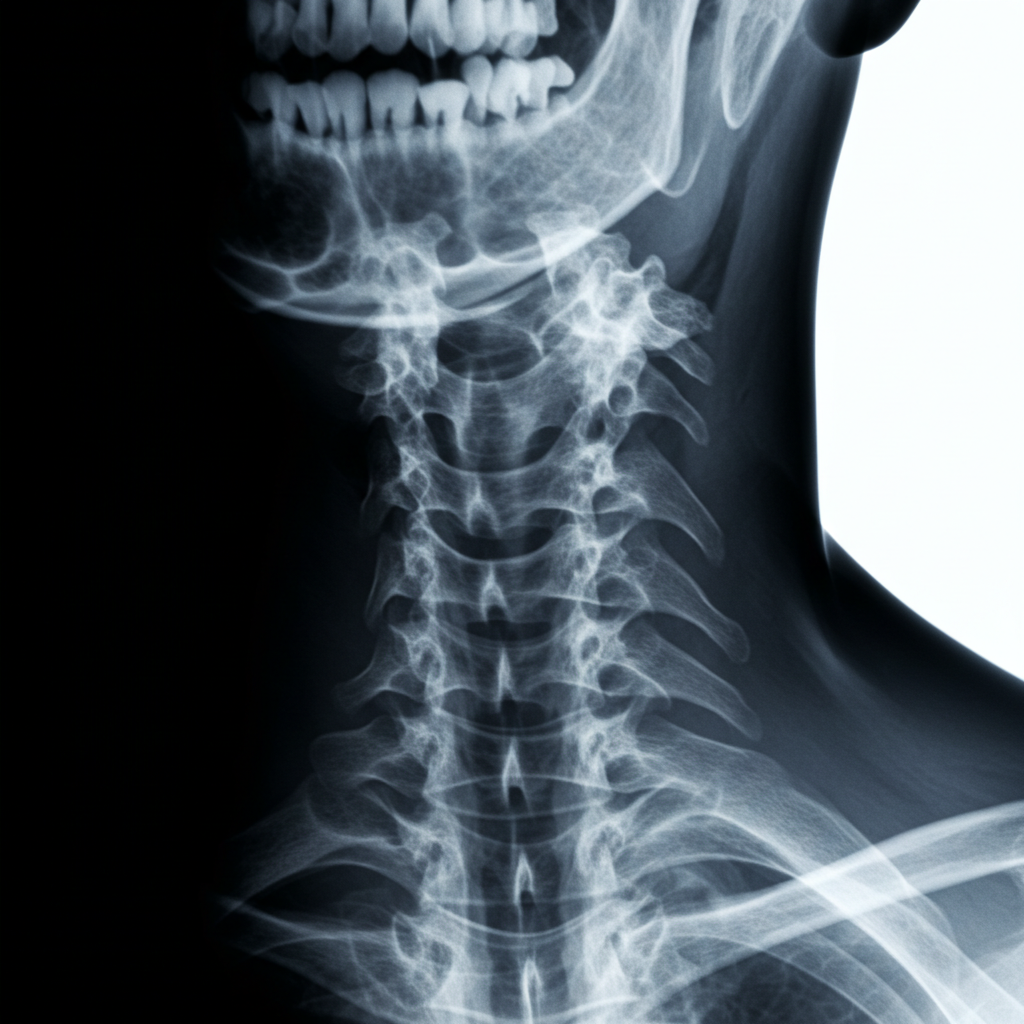

Рентген шейного отдела позвоночника – это распространенный и информативный метод диагностики, позволяющий оценить состояние костных структур шеи, выявить травматические повреждения, дегенеративно-дистрофические изменения и другие патологии. Назначение рентгена шеи осуществляется врачом на основании клинических проявлений, анамнеза пациента и результатов первичного осмотра.

Во время процедуры пациент обычно находится в положении стоя или сидя перед рентгеновским аппаратом. Рентген-лаборант может попросить принять определенные положения для получения снимков в различных проекциях (прямой, боковой, косой). Процедура занимает несколько минут и является безболезненной.